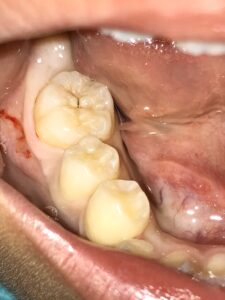

右下の奥歯に一見小さそうな虫歯を見つけました。

しかし治療を始めてみると

うーん、深い…( ̄▽ ̄;)

青く染まっているところが虫歯で歯が溶けてしまっているところです。

虫歯をすべてとると歯の神経が見えてきてしまいました。

写真の赤い部分が神経が見えてしまっているところです。

しかし、神経はまだ痛んでおらず神経を残す方針で治療を行うことにしました。